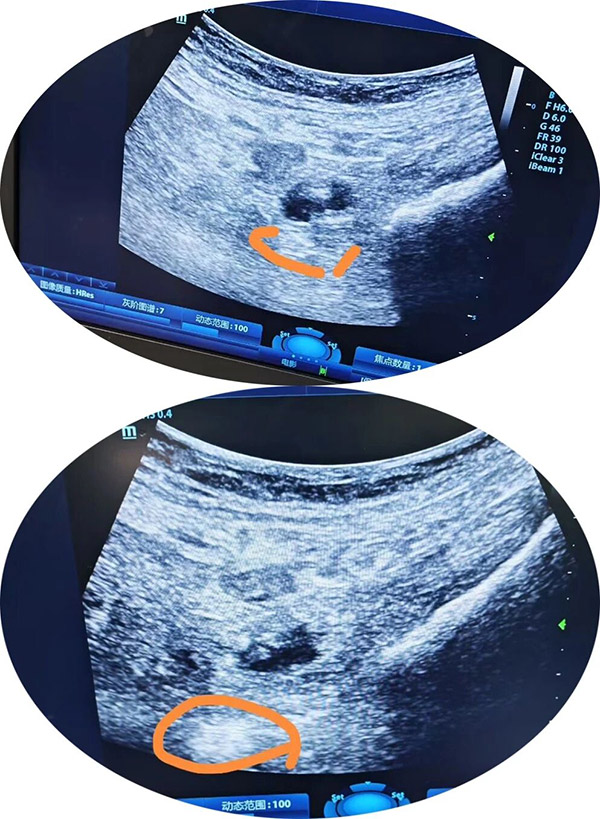

面对如此复杂的病例,综合麻醉科团队高度重视,与骨创伤与关节科朱永主任团队紧密协作,术前全面评估患者情况,认为虽麻醉风险较高,但麻醉无绝对禁忌。与外科充分沟通后,科室制定了详尽的个体化麻醉方案,决定采用:前路骶丛神经阻滞+PENG复合浅静脉麻醉,同时进行心排量及麻醉深度监测,并针对可能出现的风险做好充分预案。